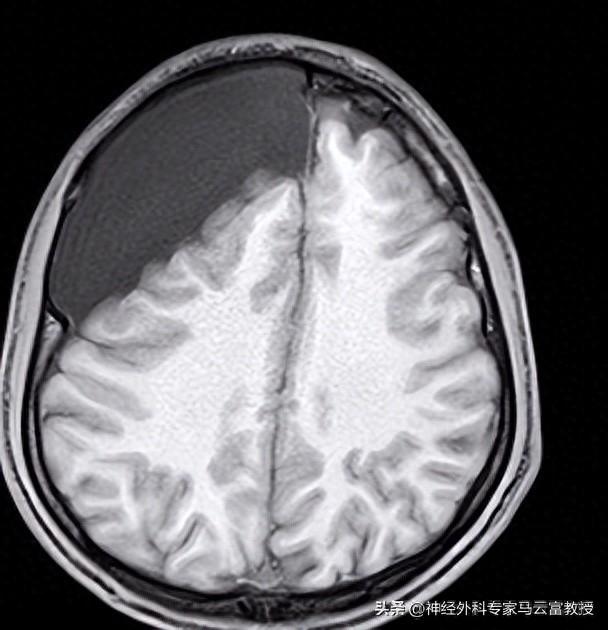

• 首選MRI(磁共振成像):這是金標準,能清楚看到囊腫的位置、大小和形狀。MRI沒有輻 射,對大腦細節顯示超級清晰。檢查時間半小時左右,躺在機器裏別動就行。

• CT掃描:如果MRI不方便,CT也能用。它更快,但有少量輻射,通常用於急診。